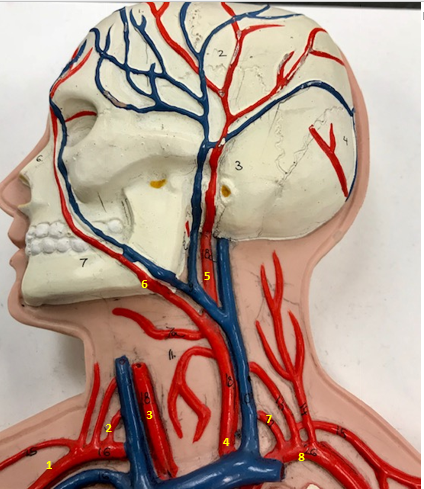

Right subclavian artery

Name #1

Supplies blood to right arm and shoulder

Function of right subclavian artery (1)

Right vertebral artery

Name #2

Supplies blood to brain and spinal cord

Function of right vertebral artery (2)

Right common carotid artery

Name #3

Supplies blood to right neck and head

Function of right common carotid artery (3)

Left common carotid artery

Name #4

Supplies blood to left neck and head

Function of left common carotid artery (4)

Left external carotid artery

Name #5

Supplies blood to face neck and skull

Function left external carotid artery (5)

Left facial artery

Name #6

Supplies blood to face and neck

Function of left facial artery (6)

Left vertebral artery

Name #7

Supplies blood to brain and spinal cord

Function of left vertebral artery (7)

Left subclavian artery

Name #8

Supplies blood to left arm and shoulder

Function of left subclavian artery (8)